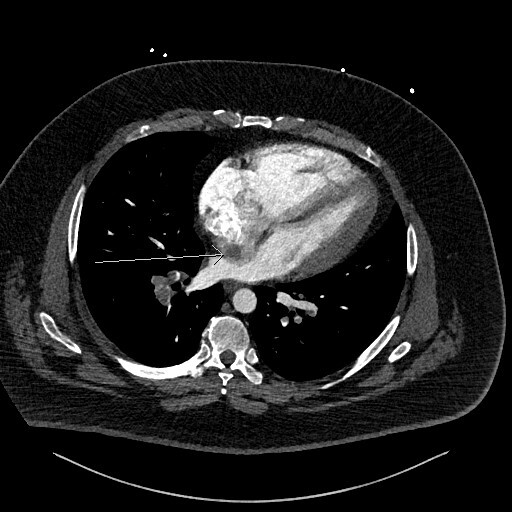

Figure 4 is a coronal image and shows the thrombus in transit again with a “boomerang” shape across the IAS (arrow heads).